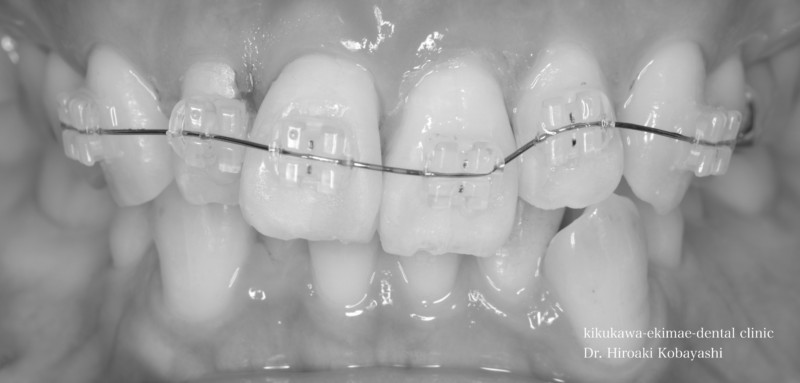

歯並びを気にされて来院されました。見た目改善を目的にワイヤーによる部分矯正を希望されました。 ブラケット装着用のマウスピースを作り、ブラケット装着を行います。   弱い力をかけながら、ワイヤーにより歯を動かします。強い力を急にかけると歯の根が吸収されてしまいます。なので弱い力で歯を動かすことによって根への負担が少なく歯根吸収のリスクが少なくなります。               6ヶ月程度で歯の並びを改善することができました。   before after